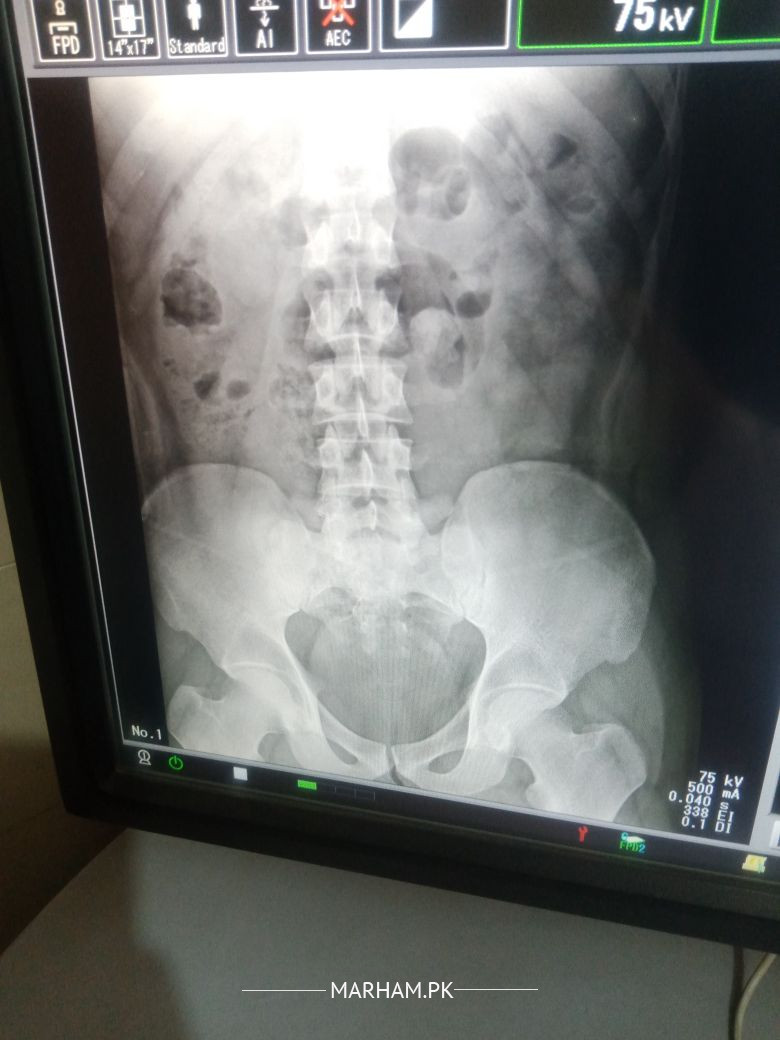

Asking For Self, Male 34, Islamabad

mere back peet pe or pait k sides par pain hota hain x-ray keia Hain result bta den

Looks straightening of spine in lateral view probably due to muscle spasm.

Better to see any orthopedic Surgeon near you for proper assessment and than management